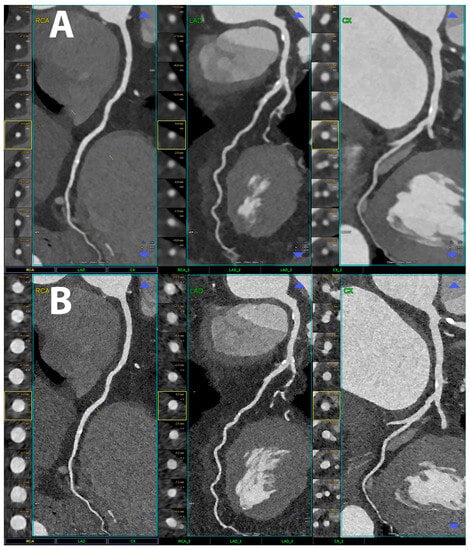

5.1. Coronary Lumen Detection

- Si-Mohamed, S.A.; Boccalini, S.; Lacombe, H.; Diaw, A.; Varasteh, M.; Rodesch, P.-A.; Dessouky, R.; Villien, M.; Tatard-Leitman, V.; Bochaton, T.; et al. Coronary CT Angiography with Photon-counting CT: First-In-Human Results. Radiology 2022, 303, 303–313. [Google Scholar] [CrossRef]